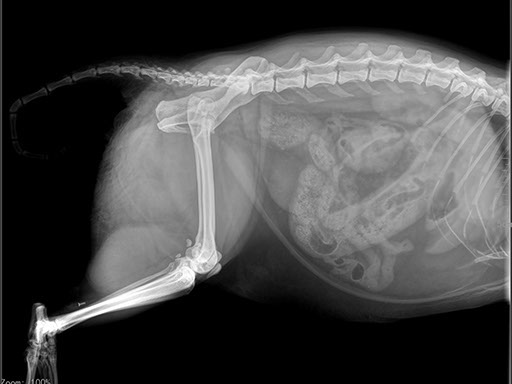

Цифровая рентгеновская установка ASR-6150C поставляется с мобильным столом пациента и комплектом рентгенопрозрачных анатомических ложементов всех размеров, видов и пород домашних животных.